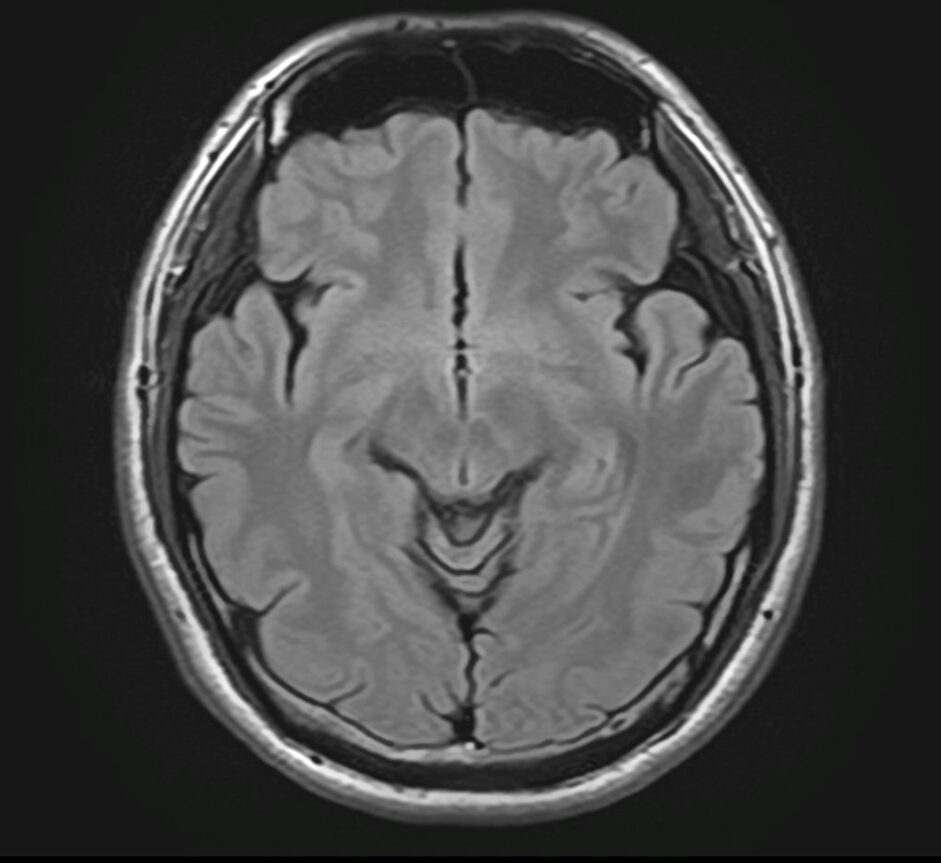

4.【画像解説】MRIでわかる副鼻腔炎と脳の状態

当院では、頭痛の原因を特定するためにMRI検査を実施しています。

MRI検査の最大のメリットは、「鼻が原因の頭痛」と「脳疾患が原因の頭痛」を一度の検査で同時に、かつ詳細に判別できる点にあります。

【MRIでどこを見るのか】

MRI画像では、脳や脳血管はもちろん、鼻の奥にある空洞を精査します。

健康な状態: 空気が入っているため、炭のように「真っ黒」に映ります。

副鼻腔炎の状態: 膿や粘膜の腫れがある部分は、「白く濁った雲」のように映し出されます。